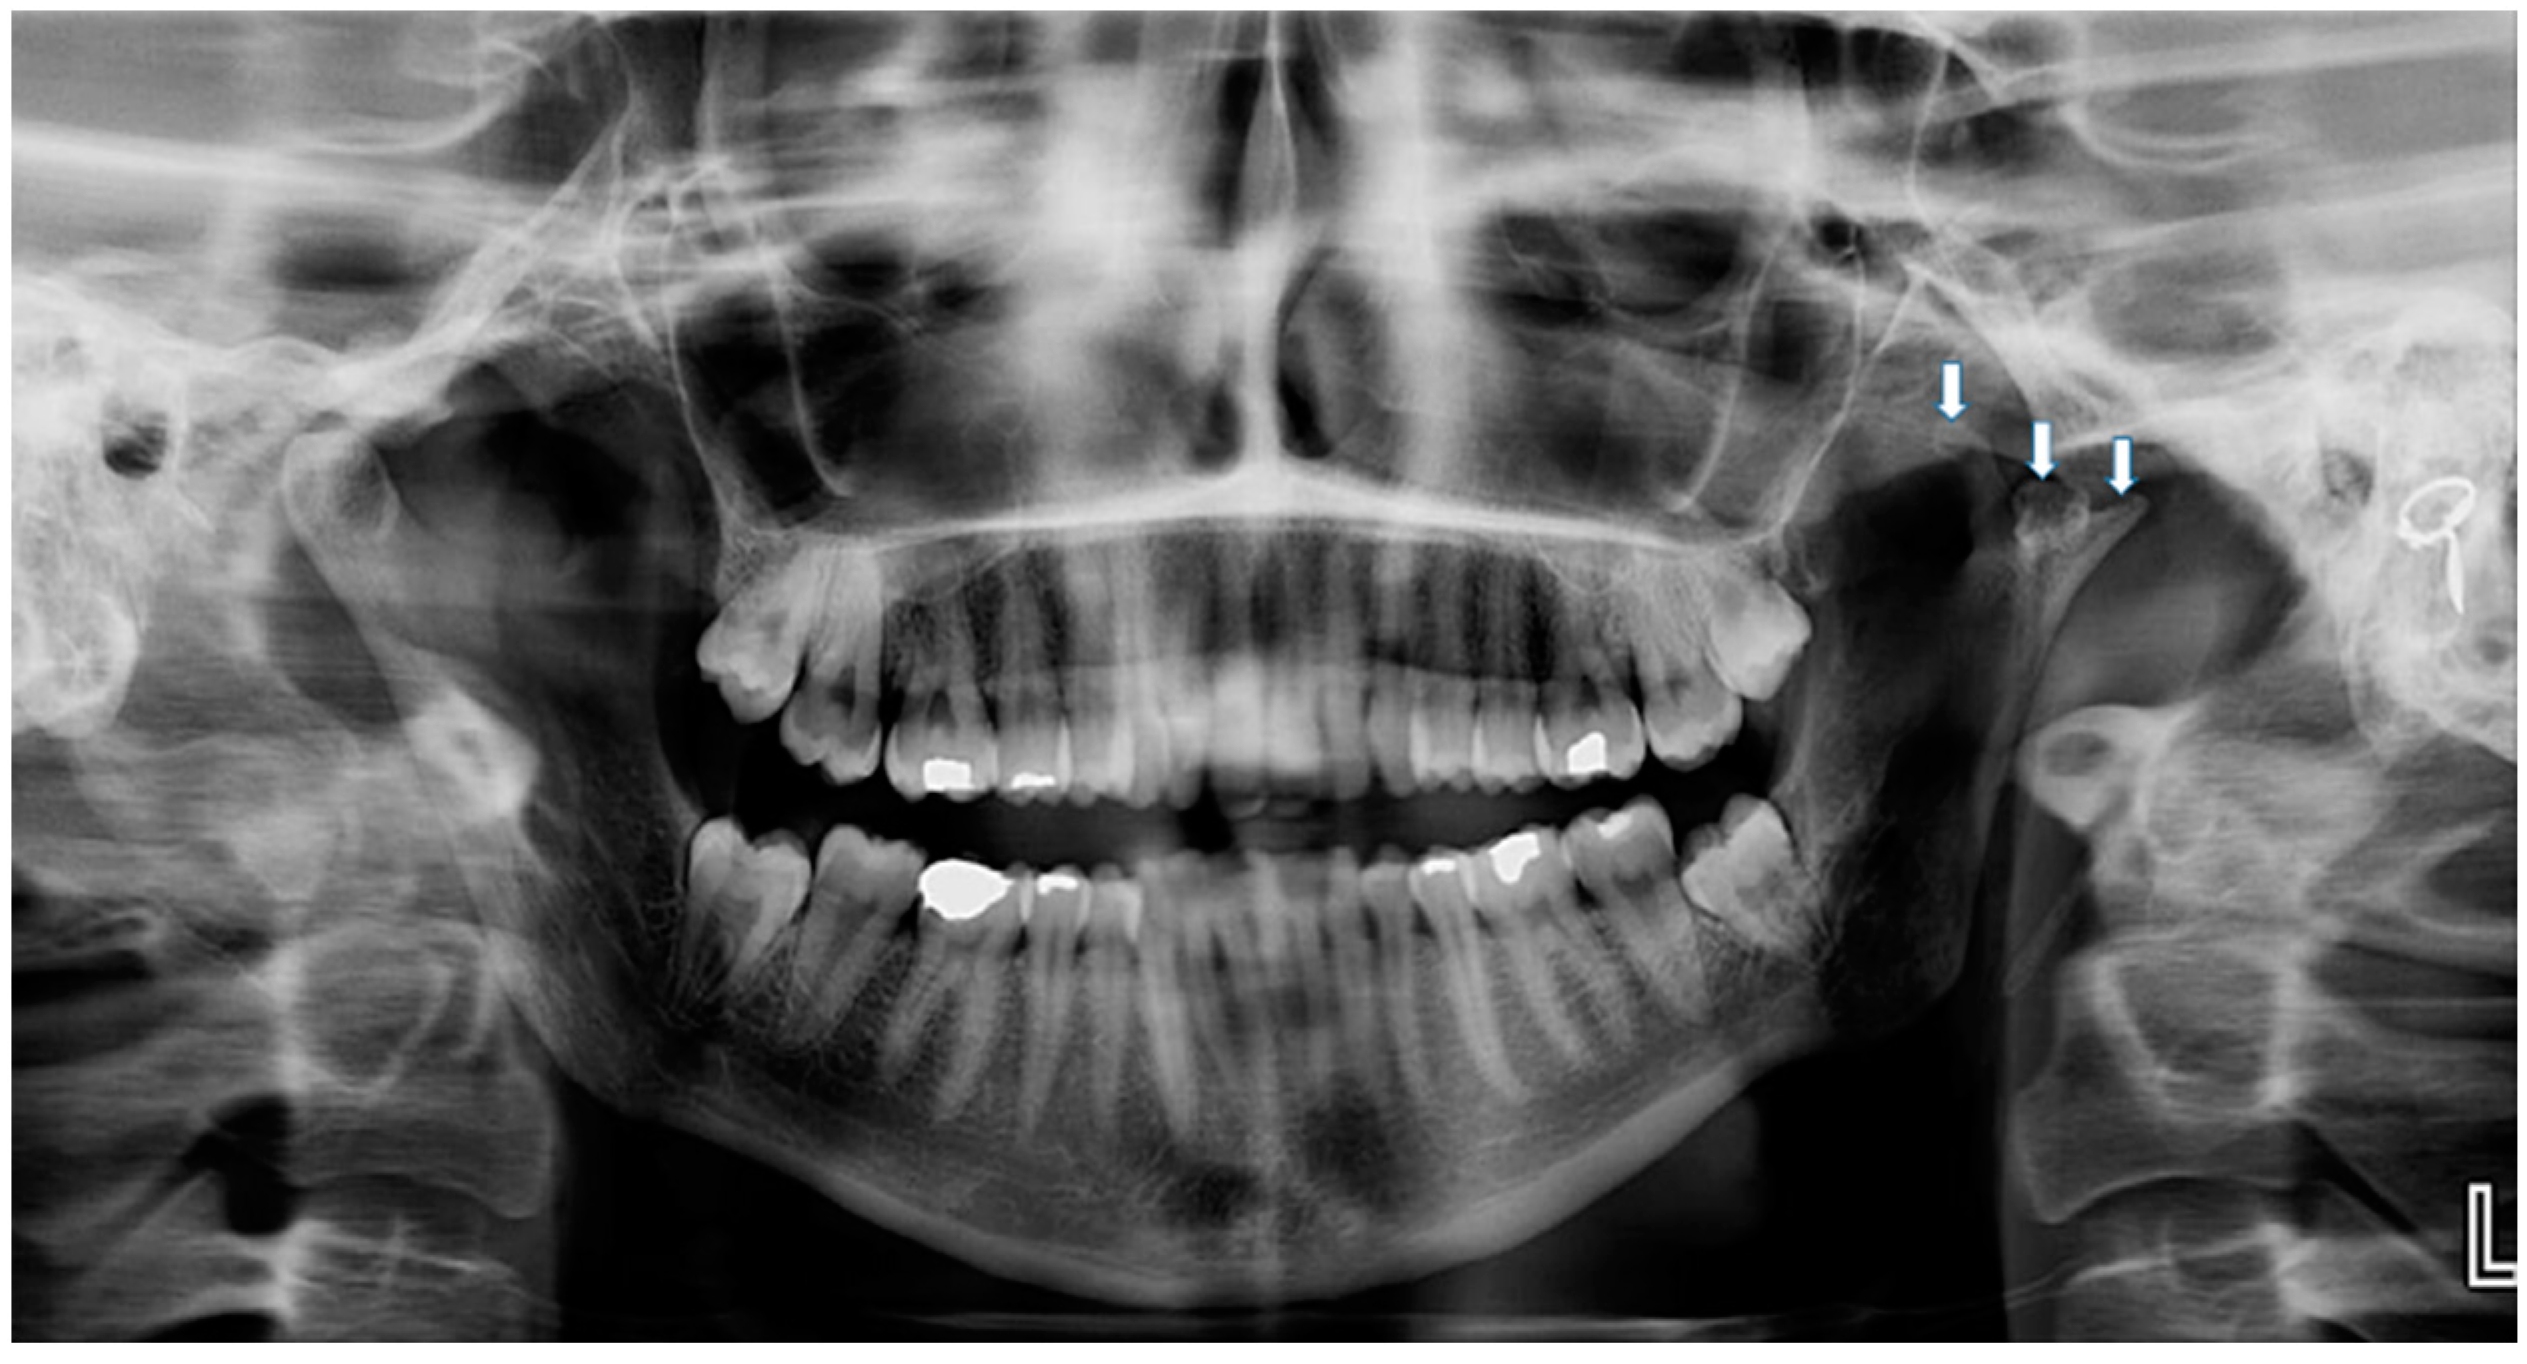

Trifid Mandibular Condyle: Case Report and Current Review of the Literature

2. Case Report

| Prasanna T. et al., 2015 [1] | F, 26 | Mild facial asymmetry, micrognathia & deviation of the mandible to left | - | None | - |

| Hernández-Andara A. et al., 2017 [8] | M, 12 | Facial asymmetry & a clicking noise in the left TMJ | Trauma | FU | - |